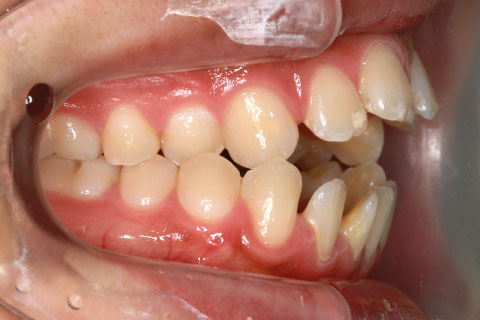

症例1

治療前

年齢・性別

23歳女性

治療期間

1年4ヶ月

抜歯

なし

治療費

80万(税込)

備考

マルチブラケットを用いた矯正治療

治療内容

前歯の開口を顎間ゴムにて改善

施術の副作用(リスク)

舌の癖や鼻疾患がある時は、後戻りを起こすことがあります。